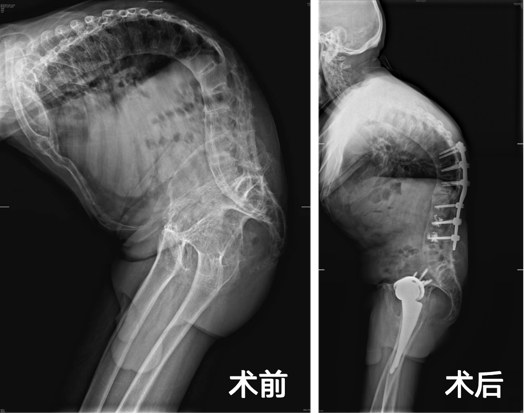

面对林老伯的病情,骨科与运动医学中心组织了脊柱外科、风湿骨病科、麻醉科等多学科专家进行MDT(多学科诊疗)会诊,最终决定为他分两次手术,先进行双侧全髋关节置换术,再行L1 COWO截骨+T10-L4椎弓根钉棒内固定术。

二期手术决战脊柱矫形,团队将林老伯腰椎“打断重生”,植入钛合金螺钉,手术顺利完成,术后林老伯一共挺高了40cm,疼痛也明显缓解。“真的太感激专家了。”林老伯感激不已。

术前、术后影像对比图